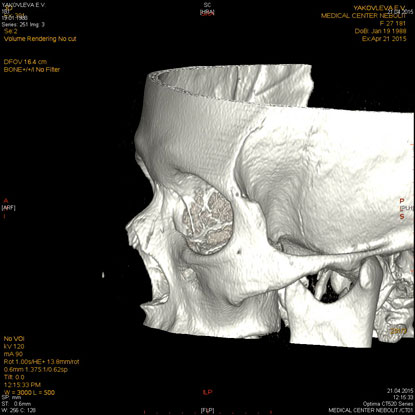

МСКТ придаточных пазух носа, лицевого черепа, орбит

Показания:

- подозрение на опухоль, кисту

- воспалительные заболевания при отсутствии эффекта от бактериальной терапии

- травма

- аномалии развития

Подготовка: не требуется.

Предварительное рекомендуемое обследование: заключение оториноларинголога